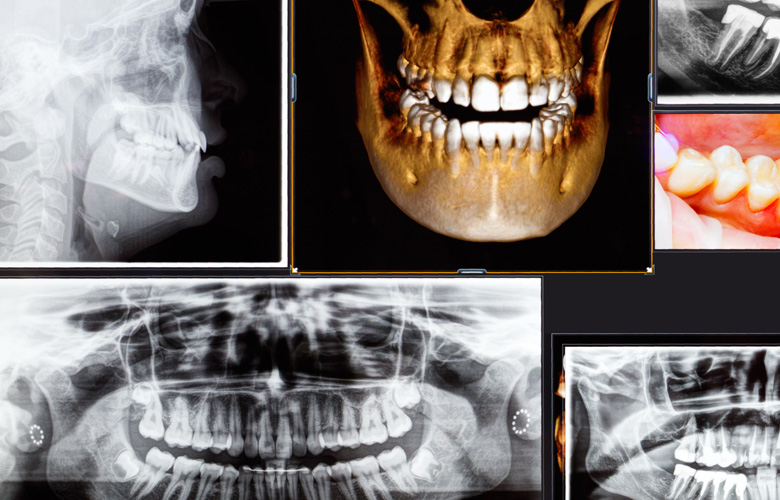

歯科用CTを導入し、根管治療・インプラント治療・親知らずの抜歯・歯牙移植の際などに用いております。従来のレントゲン撮影では平面的(2次元的)な画像しか撮影できないのですが、歯科用CTでは立体的(3次元的)な画像撮影や任意の位置や角度からの歯や骨の画像を確認できます。そのためより精度の高い検査・診断及び質の高い治療を行うことにつながるのです。

特に歯牙移植を行なううえで、歯科用CTによる検査・診断は必要不可欠です。

移植する歯の大きさや、移植する場所などのレントゲン撮影が精度高くできるため、治療の精度が高まります。

歯科用CTは、立体的(3D)な歯や骨の画像を確認できます。

歯や骨の形や位置が通常のレントゲンよりも精度高く撮影できるため、治療の精度が高まります。